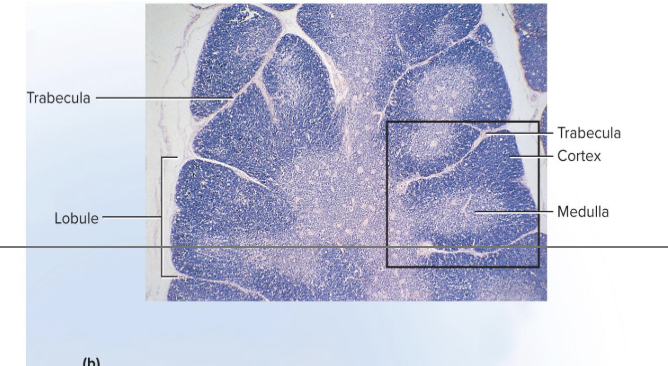

Thymus Structure

• has trabeculae (septa) that divide the gland into several lobes

<ul><li><p>has trabeculae (septa) that divide the gland into several lobes</p><ul><li><p>Lobes have a cortex and a medulla populated by T lymphocytes</p></li></ul></li></ul><ul><li><p>Epithelial cells seal off cortex from medulla forming a <strong>blood–thymus barrier</strong></p></li><li><p>Produce signaling molecules that regulate the immune system</p><ul><li><p>thymosin, thymopoietin, thymulin, interleukins, and interferon</p></li></ul></li></ul><p></p>